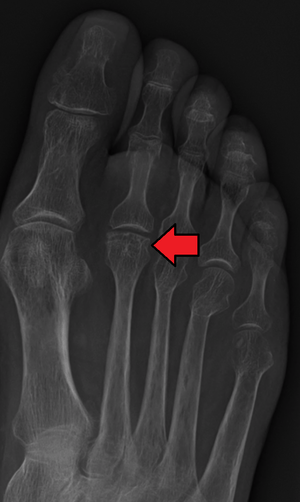

| Freiberg disease as seem on plain film | |

Freiberg disease, also known as a Freiberg infraction, is a form of avascular necrosis in the metatarsal. It generally develops in the second metatarsal, but can occur in any metatarsal. Physical stress causes repeated microfractures where the middle of the metatarsal meets the growth plate. These restrict circulation to the end of the metatarsal, causing the necrosis. It is an uncommon condition, occurring most often in young women, athletes, and those with abnormally long metatarsals. Approximately 80% of those diagnosed are women.[1]